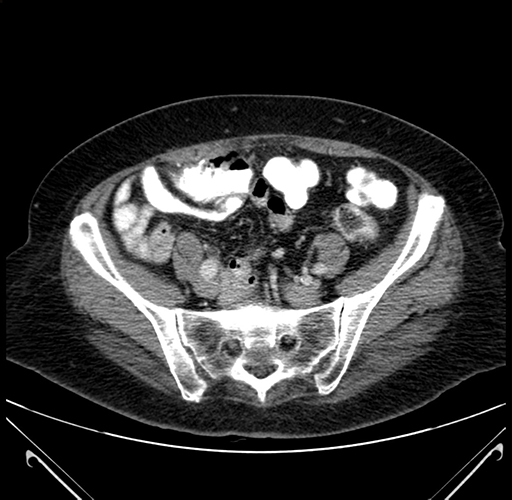

Pre-Chemo: Axial Venous

Axial Venous